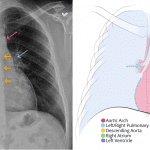

Chest radiograph & CT anatomy